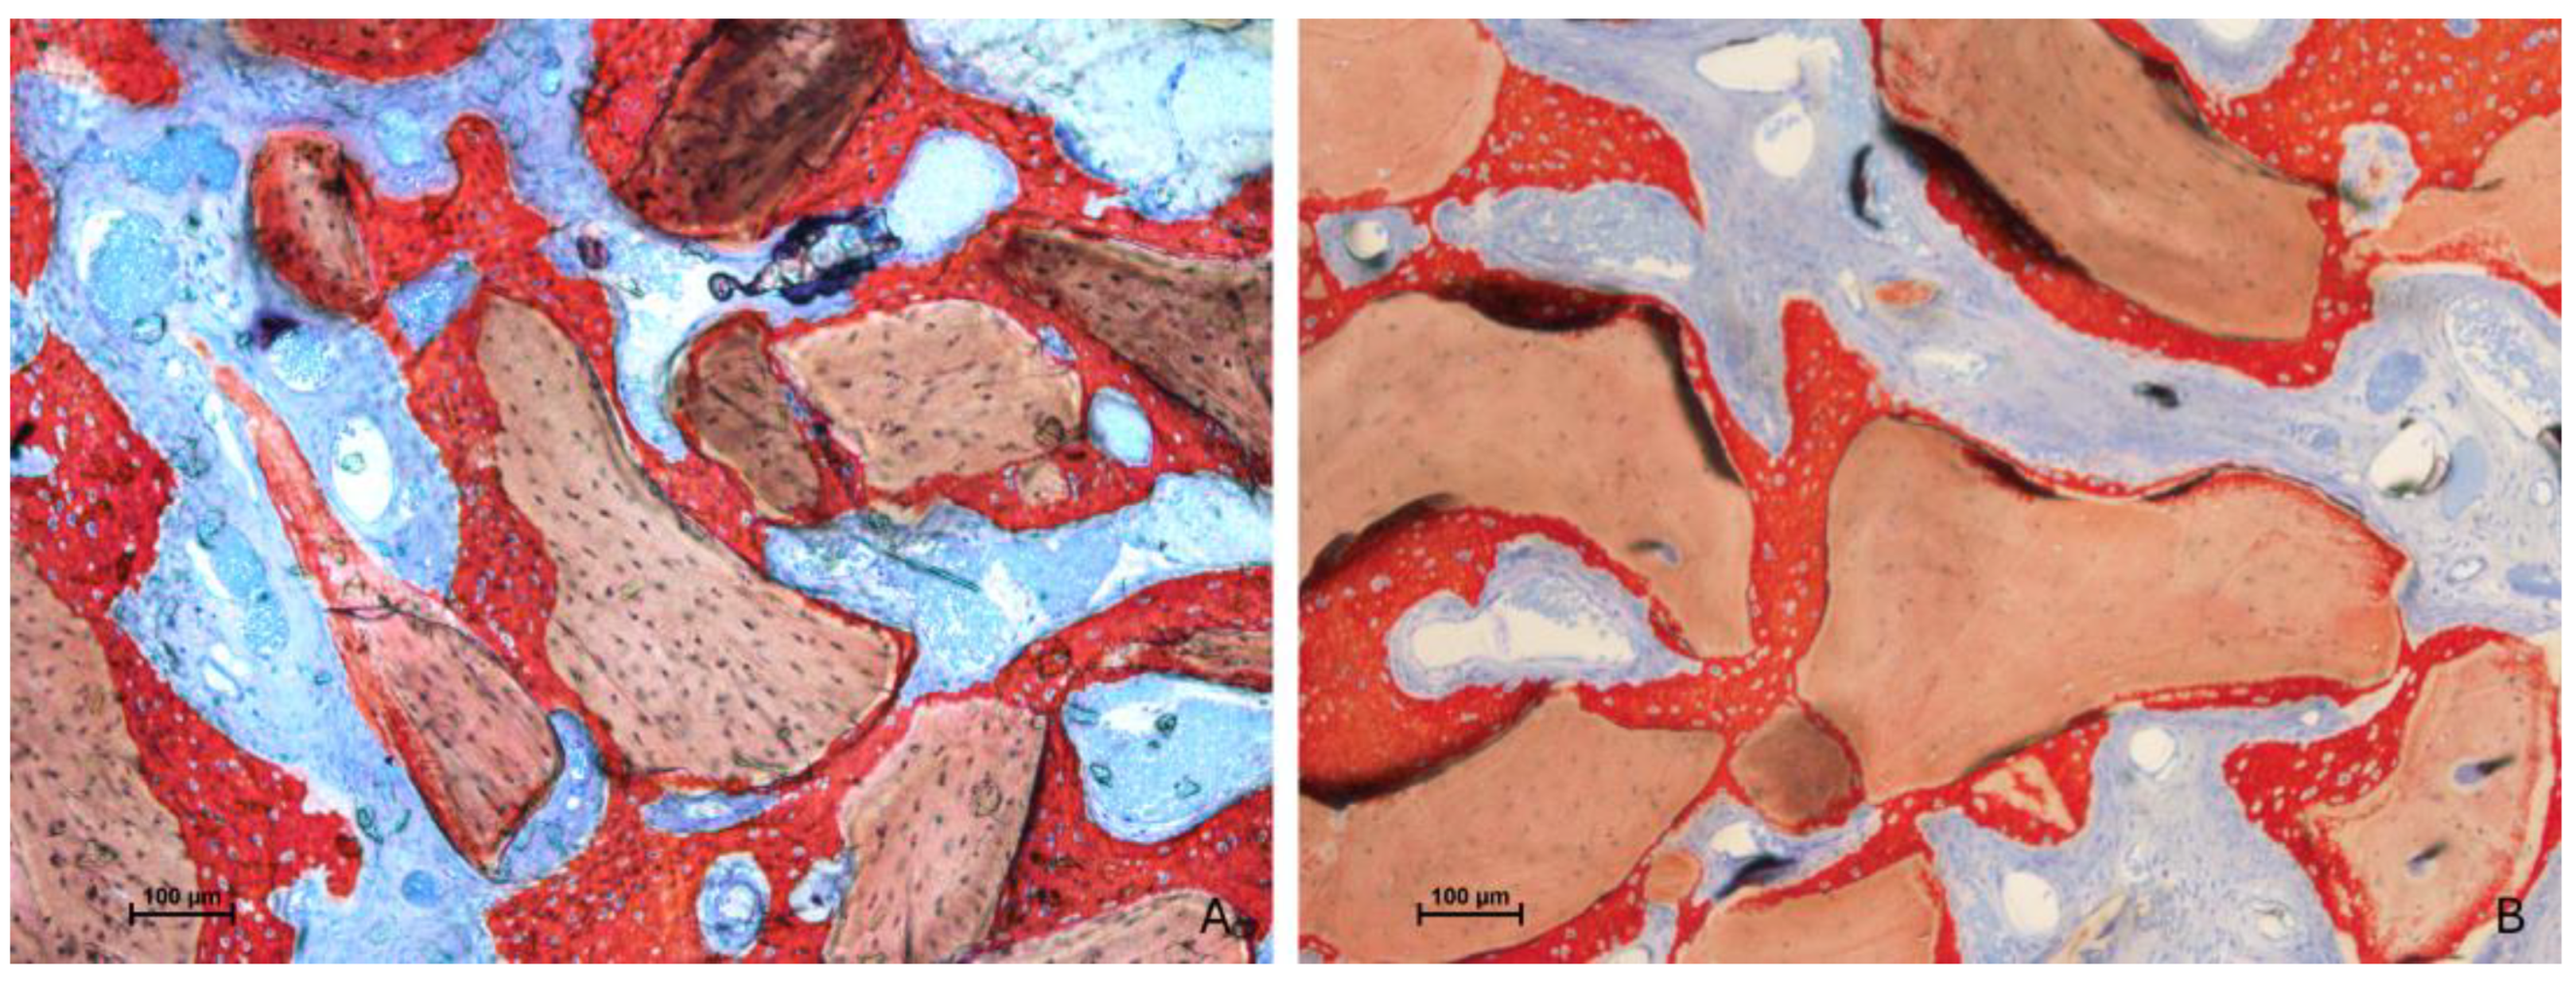

3.2. Descriptive Histological Evaluation